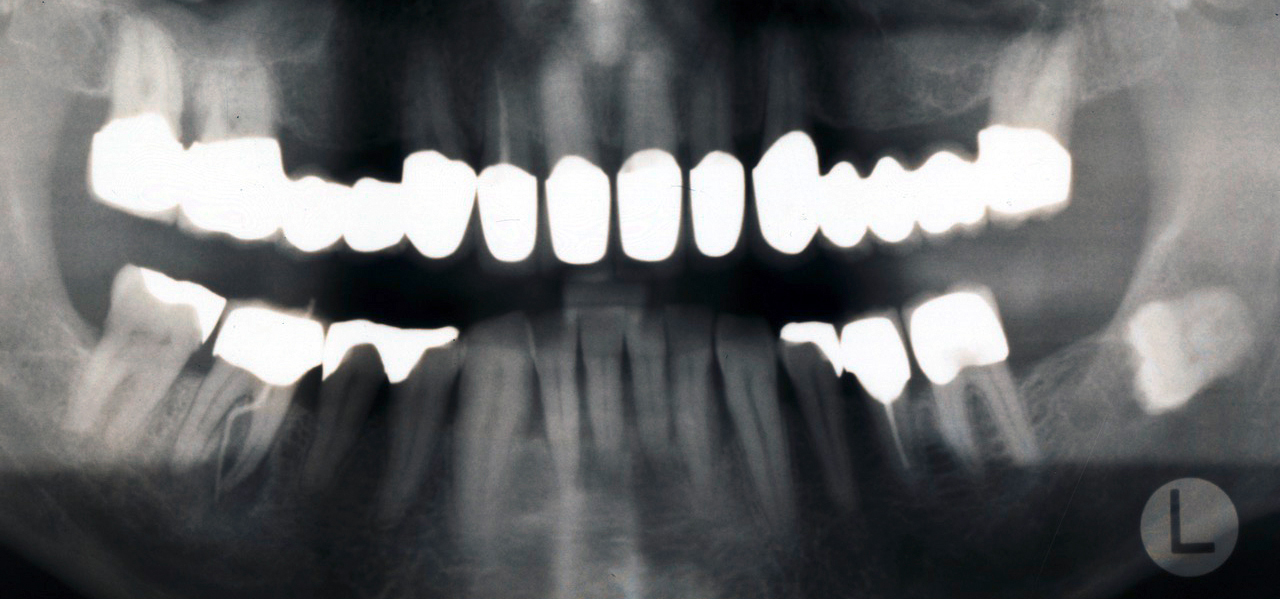

Eine professionelle Zahnreinigung (PZR) ist hilfreich, weil sich auf gereinigten Zähnen Plaque (Zahnbelag) leichter im Zaum halten lässt; Plaquefreiheit von eigener Hand herzustellen, ist mühsamer. Stellt der Zahnarzt einen Code 3 (Zahnfleischtaschen von 3,5 bis 5,5 mm) oder sogar Code 4 (Zahnfleischtaschen tiefer als 5,5 mm) fest, muss allerdings eine gründliche Untersuchung durchgeführt werden, um das Ausmaß der Erkrankung und den Behandlungsumfang feststellen zu können. Dafür werden die Zahnfleischtaschen und der Gewebeverlust an allen Zähnen gemessen und Röntgenbilder angefertigt.

Eine erfolgreiche Behandlung der parodontalen Entzündung kann nicht nur die lokalen Symptome der Erkrankung des Zahnhalteapparats und damit Zahnverlust vermindern (s. Abb. 3 u. 4), sondern auch die Stoffwechseleinstellung verbessern. Die Reduktion des HbA1c-Werts lag bei Typ-2-Diabetikern drei Monate nach einer nichtchirurgischen Parodontitisbehandlung zwischen 0,4 und 0,5 Prozent, was durchaus nennenswert ist.